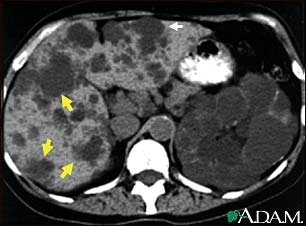

This abdominal CT scan shows cysts in the liver and kidneys (polycystic disease). The liver is the large organ on the left side of the screen. The dark spots in the liver are cysts.